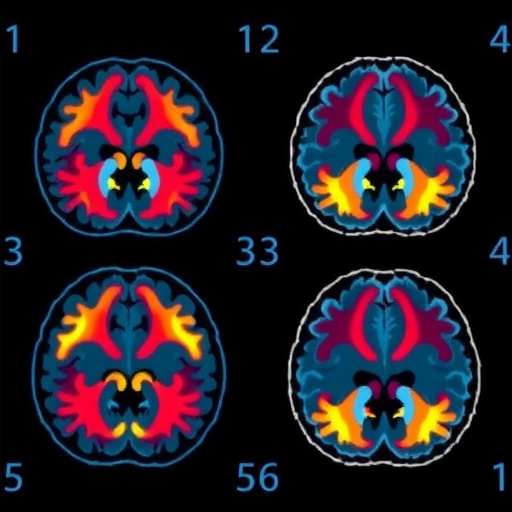

At the heart of this study lies the amygdala, a critical brain structure known as the brain’s “alarm button.” The amygdala orchestrates our instinctive responses to perceived threats, firing up to alert us of danger. Prof. Miskowiak’s team utilized functional magnetic resonance imaging (fMRI) to observe amygdala activity in 112 participants diagnosed with depression or bipolar disorder. Subjects were exposed to images of faces expressing happiness or fear, allowing researchers to quantify real-time neural responses to these emotional signals. This neuroimaging approach enabled them to pinpoint differences in how intensely individuals processed threatening stimuli.

Longitudinal follow-up over twelve months established a compelling link between these neural and behavioral markers and the risk of subsequent psychiatric hospitalization. Those exhibiting stronger amygdala activation specifically in response to fearful faces faced a statistically significant increase in readmission risk. Moreover, individuals who more rapidly detected negative emotions relative to positive ones similarly showed elevated vulnerability to illness exacerbation requiring hospital care. This association transcended diagnostic categories, applying to both depressive and bipolar disorders, suggesting a shared neurobiological vulnerability underpinning affective dysregulation.

The concept of a “negativity bias” emerged prominently in these findings, reflecting a tendency for the brain to amplify responses to negative emotional information while potentially disregarding neutral or positive signals. Such a skewed interpretative lens could cause patients to misread environmental cues as more threatening than they truly are, precipitating stress and symptom deterioration. Quantitatively, each incremental increase in amygdala reactivity to threat correlated with a 17% higher likelihood of hospitalization, underscoring the clinical relevance of this neurophysiological marker.